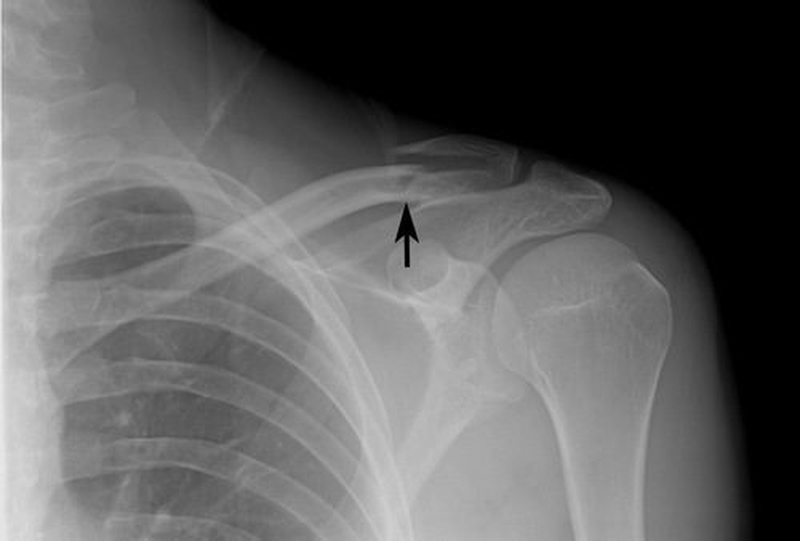

Gãy xương đòn còn được biết đến là gãy xương quai xanh, đây là phần xương giữa cổ và vai, theo chiều ngang giữa đỉnh xương ức và xương bả vai. Ngoài việc điều trị bằng các phương pháp chuyên khoa, bạn cũng nên lưu ý đến việc gãy xương đòn nên ăn gì để giúp xương mau lành cũng như giảm đau nhức.

Gãy xương đòn là tình trạng chấn thương thường gặp xảy ra đặc biệt ở trẻ nhỏ và thanh thiếu niên. Xương đòn được biết là xương nối từ phần trên của xương ức đến xương bả vai. Cũng như tình trạng gãy xương khác, nguyên nhân thường gặp phải của gãy xương đòn gồm có: Bị té, chấn thương trong khi chơi thể thao và bị tai nạn giao thông. Với trẻ sơ sinh đôi khi bị gãy xương đòn có thể trong quá trình sinh nở của người mẹ.

Gãy xương đòn nên ăn gì để mau hồi phục 1 Xương đòn vai bị gãy do nhiều nguyên nhân khác nhau